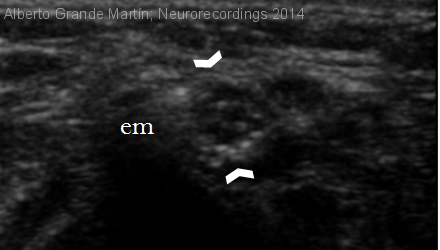

Hombre | 42 años

Diagnóstico final: Neuropatía cubital derecha grave y crónica por atrapamiento en codo